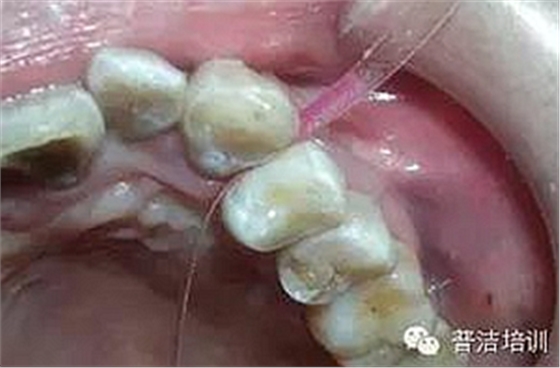

牙線去除鄰面樹脂粘結(jié)劑

鄰面拋光

粘結(jié)完成后